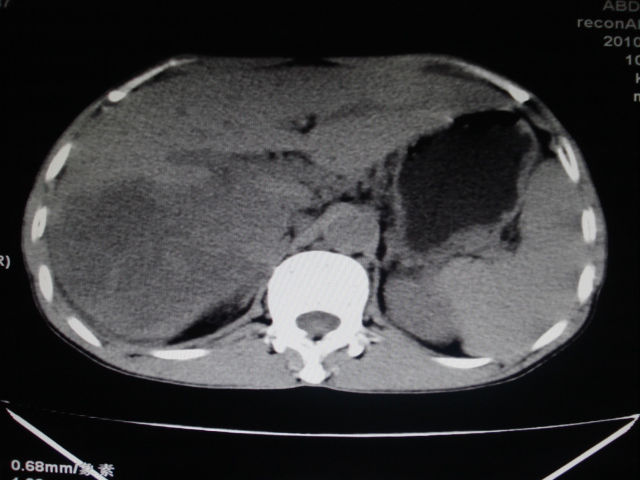

男性,62岁。肝右叶占位,平扫及增强如下,延迟期为15分钟扫描。

1)不均匀性脂肪肝。2)肝硬化。3)肝右叶肝癌不排除。4)右肾囊肿。